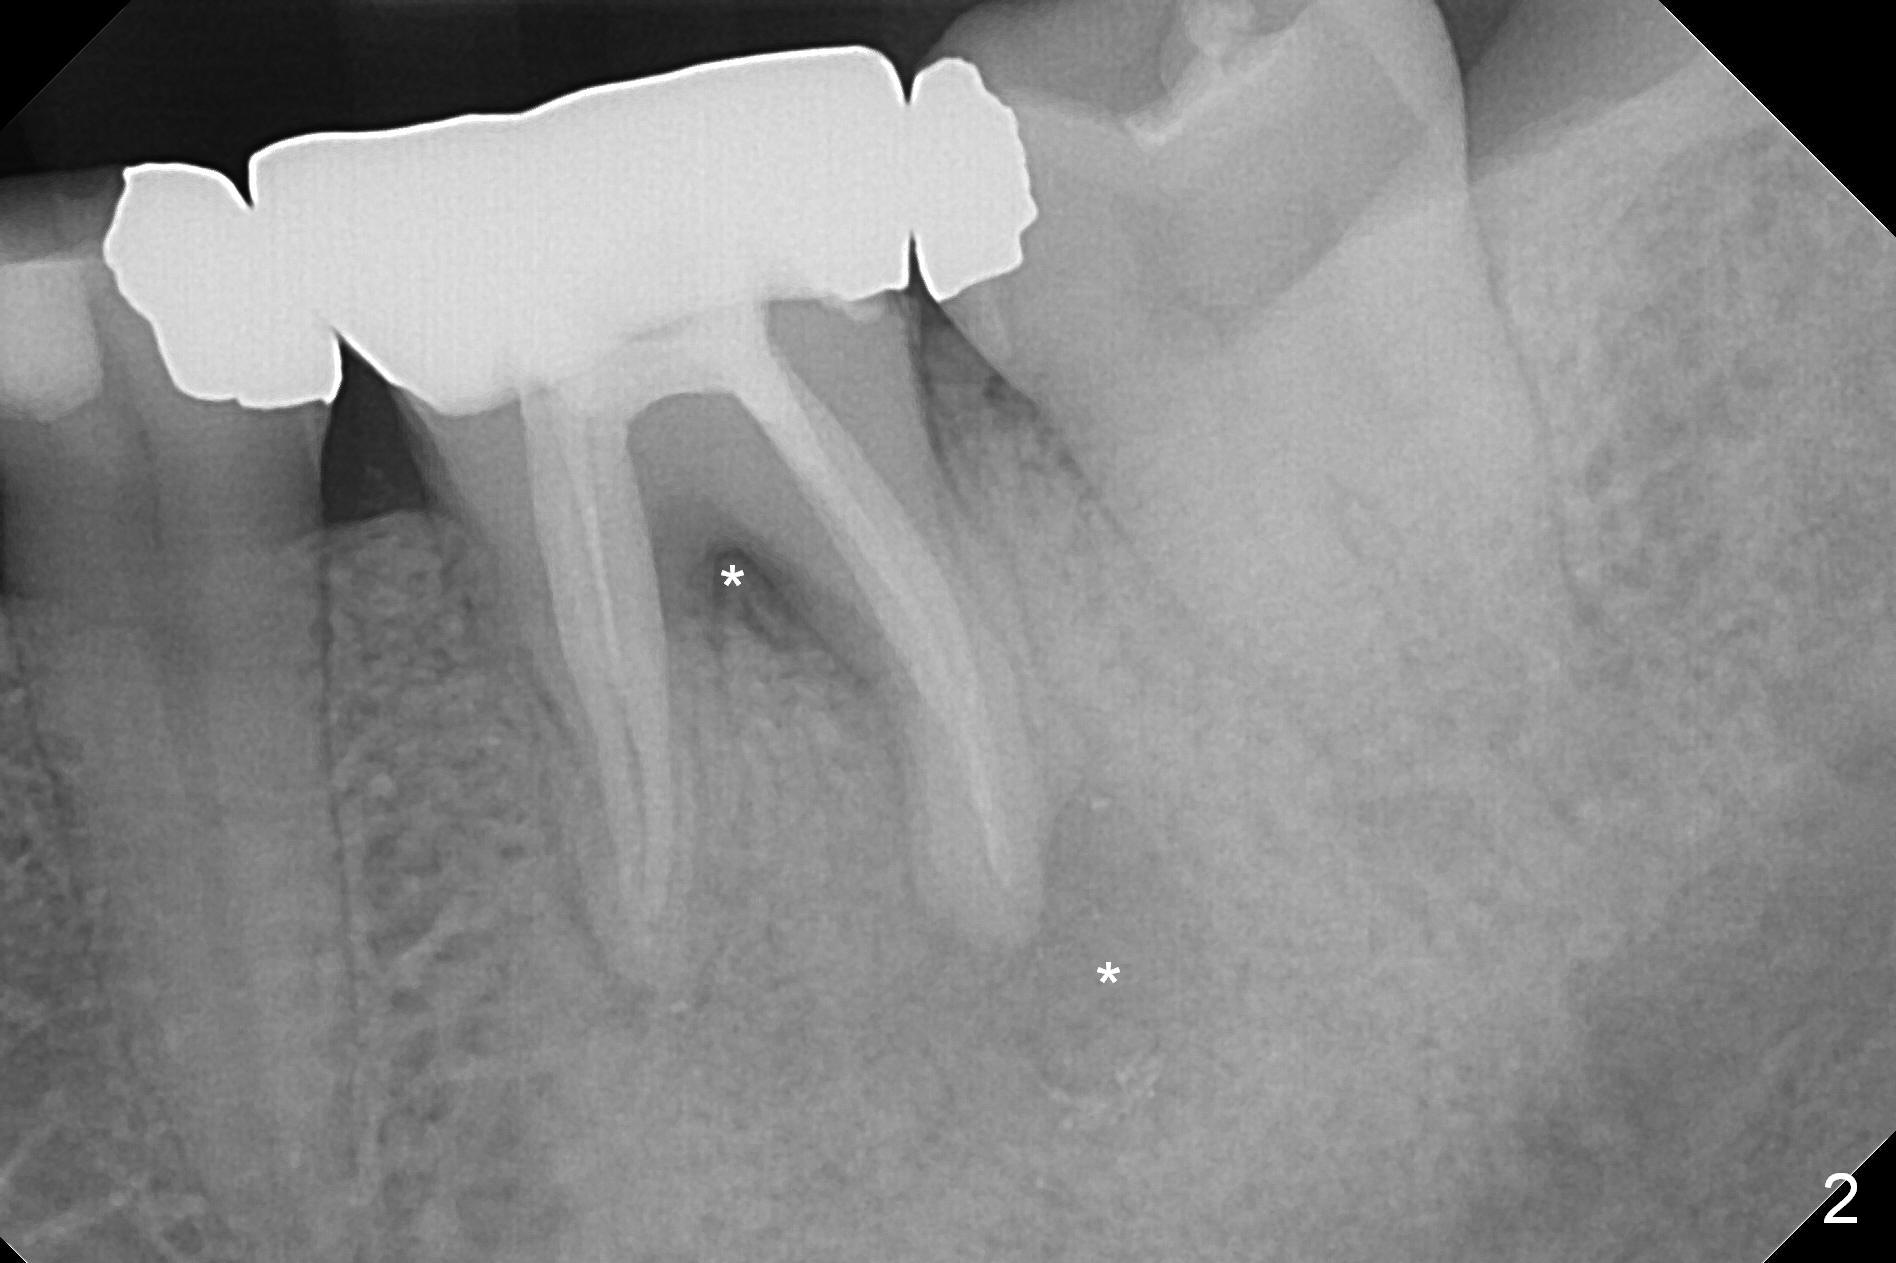

A 48-year-old woman has had mild discomfort at #19 four years post RCT (Fig.1). It appears that the tooth has 3 roots. The latter should help stabilize an implant placed in the septum (tripods). The affected tooth has large distal periapical radiolucency (Fig,2 *). There is localized swelling at the buccal furca. After debridement, treat the sockets with Clindamycin. Osteotomy will be slightly lingual, since the buccal plate is thinner than the lingual one. In addition, the buccal plate is most likely defective due to furca and periapical lesions. The longest IBS implant is going to be chosen unless the implant has to be placed deep due to furca destruction. In fact the patient has the tooth extracted in other office with socket preservation.